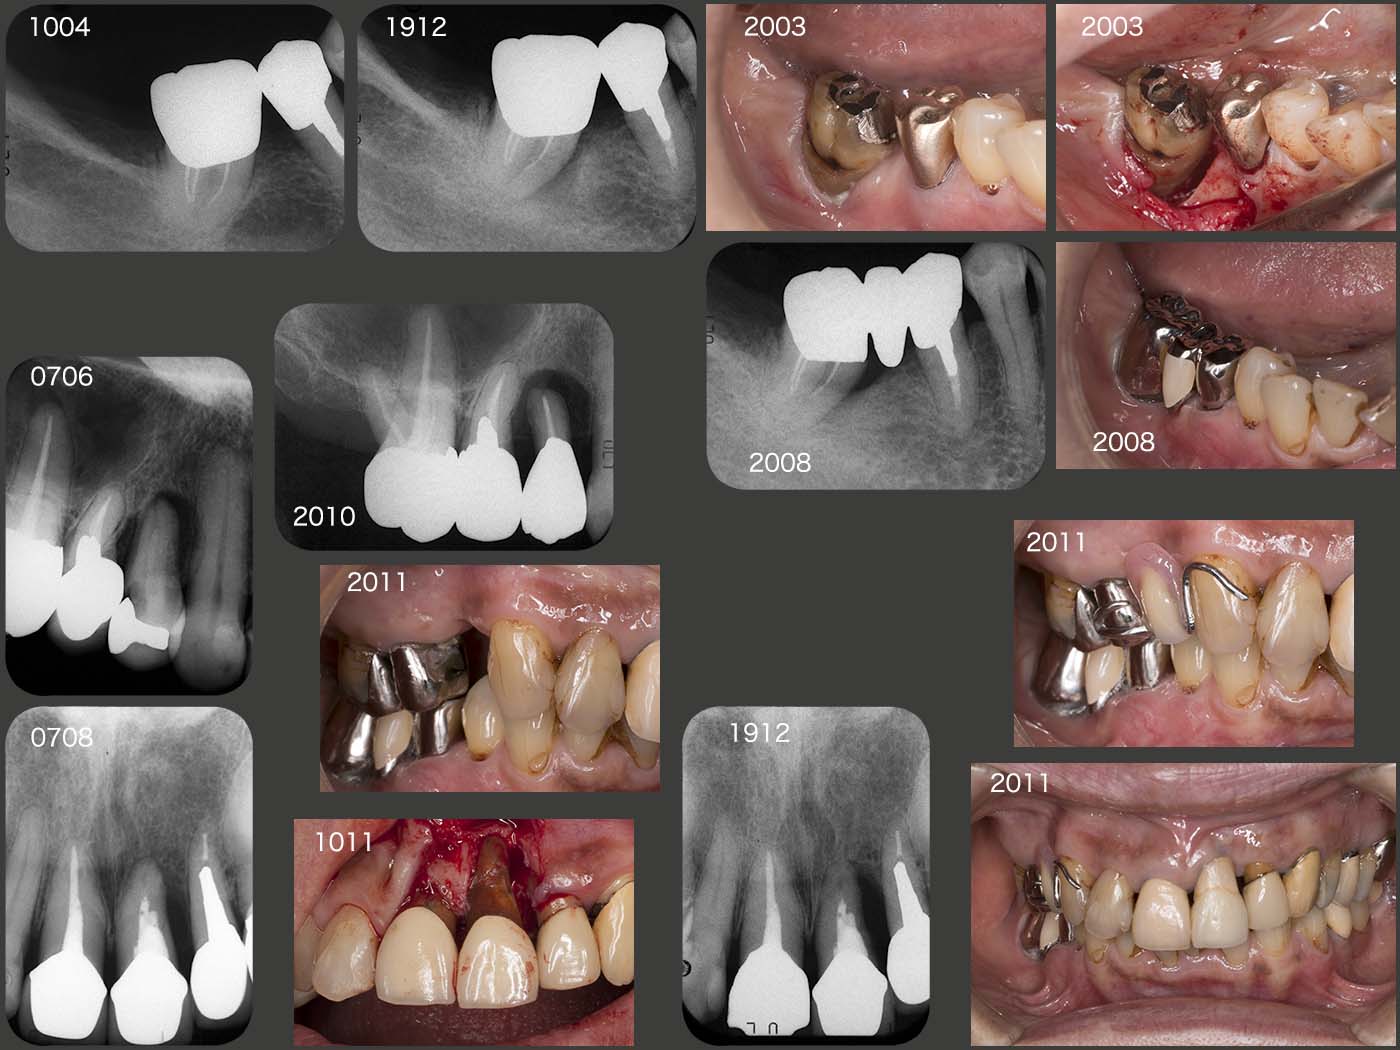

上段のパノラマX線写真は2002年4月,ブリッジ装着後5年の状態である.この時は,大臼歯部において咬合支持数の多い左側で主に咀嚼していたと思われる.05年に左側の上下7を歯周病で抜歯しているが,左側咬みが大きな要因の一つと思われる.中段は12年6月の状態.左側の上下7を抜歯してから,右側で咀嚼する頻度が増し,右下5の歯根破折に繋がったと思われる.なお,左下のスライドは,16年8月の状態.特に順調に経過しているが,つぎは,右下7に問題が生じる可能性が高いと危惧している.

2017年5月に右下7に歯根破折が生じ,抜去した.右下3にクラスプを付与していたため,右下7の外冠を人工歯として増歯するだけの改変で済んだ.

19年11月,左下5,6間のコンタクトが空いたため,左下6の修復をやり直した.なお,また空く可能性があるので,仮着するに留めた.

20年6月,習慣性咀嚼側が左側に移ったために今度は左上4の歯周病が増悪してきた.舌側の歯周ポケットが8mmの値を示したため,7月にインレーを外し,自然挻出を期待した.10月に歯周外科処置を行い,11月現在,左上4,5を暫間被覆冠で連結固定している最中である.今後,左上4,5,6のコーヌス冠を装着する予定である.